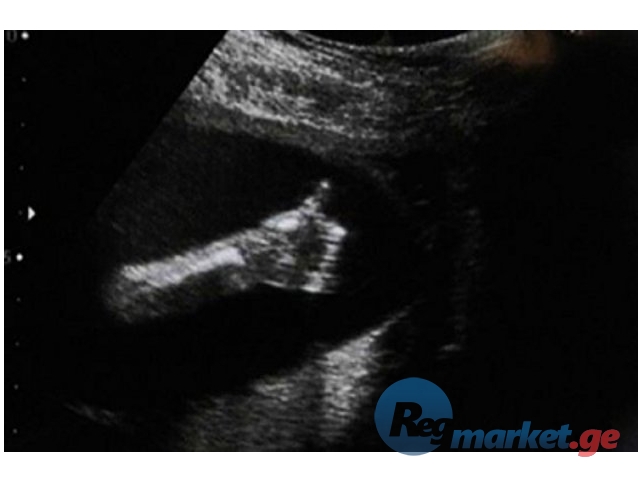

კვალიფიციური ექოსკოპიური კვლევები ბინაზე გამოძახებით (ახალი ციფრული აპარატით):

1) მუცლის ღრუს ორგანოების ექოსკოპია (სასურველია ჩატარდეს უზმოდ ან ჭამიდან 6 საათის შემდეგ), 2) საშარდე სისტემის (თირკმელები, შარდის ბუშტი), 3) პროსტატის (ტარდება გავსებული შარდის ბუშტით), 4) ტრანსაბდომინური ექოსკოპიური გინეკოლოგიური კვლევა (აუცილებლად გავსებული შარდის ბუშტით), 5) სამეანო ულტრაბგერითი გამოკვლევები ნაყოფის ბიომეტრიით, 6) ორსულობის დადგენა (დადგენა 5 კვირიდან, გავსებული შარდის ბუშტით), 7) ფარისებრი ჯირკვლის ექოსკოპია, 8) პლევრის ღრუების, 9) სათესლე ჯირკვლების, 10) რბილი ქსოვილების...

ექიმი რადიოლოგი, მედ. მეცნ. დოქტორი 18 წლიანი გამოცდილებით. http://www.vidal.ge/doctors/giorgi-chamiashvili

ერთი ექოსკოპია (კონსულტაციით, რეკომენდაციებით) 70-75 ლარი, ყოველი დამატებითი სისტემა + 10-15 ლარი... ორი პაციენტის გამოკვლევის შემთხვევაში ერთი სონოსკოპია 60 ლარი. ექიმის წაყვანის შემთხვევაში თქვენი ტრანსპორტით ერთი კვლევა 60 ლარი, ქალაქის გარედ +20 ლარიდან (მანძილის და დროის მიხედვით). შესაძლებელია პაციენტის მოყვანა ადგილზე თქვენი ტრანსპორტით - ერთი კვლევა 30 ლარიდან. 22:00-09:00 ღამის ტარიფი + 10 ლარი. სასურველია დარეკოთ წინასწარ T 555 277 077